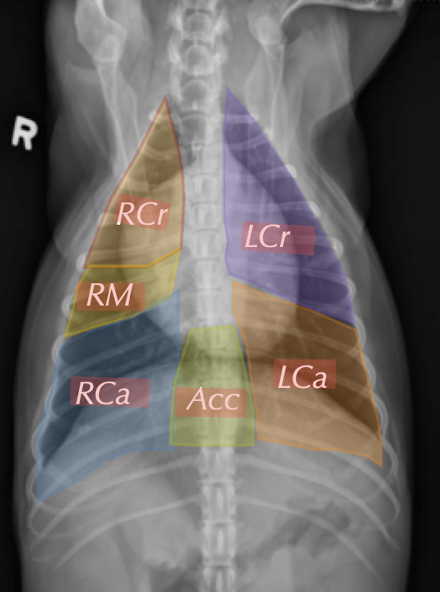

list the lobes of the lungs

What regions of the lung lobes are the colours representing?

Black: perihilar

orange: midzone

blue: periphery